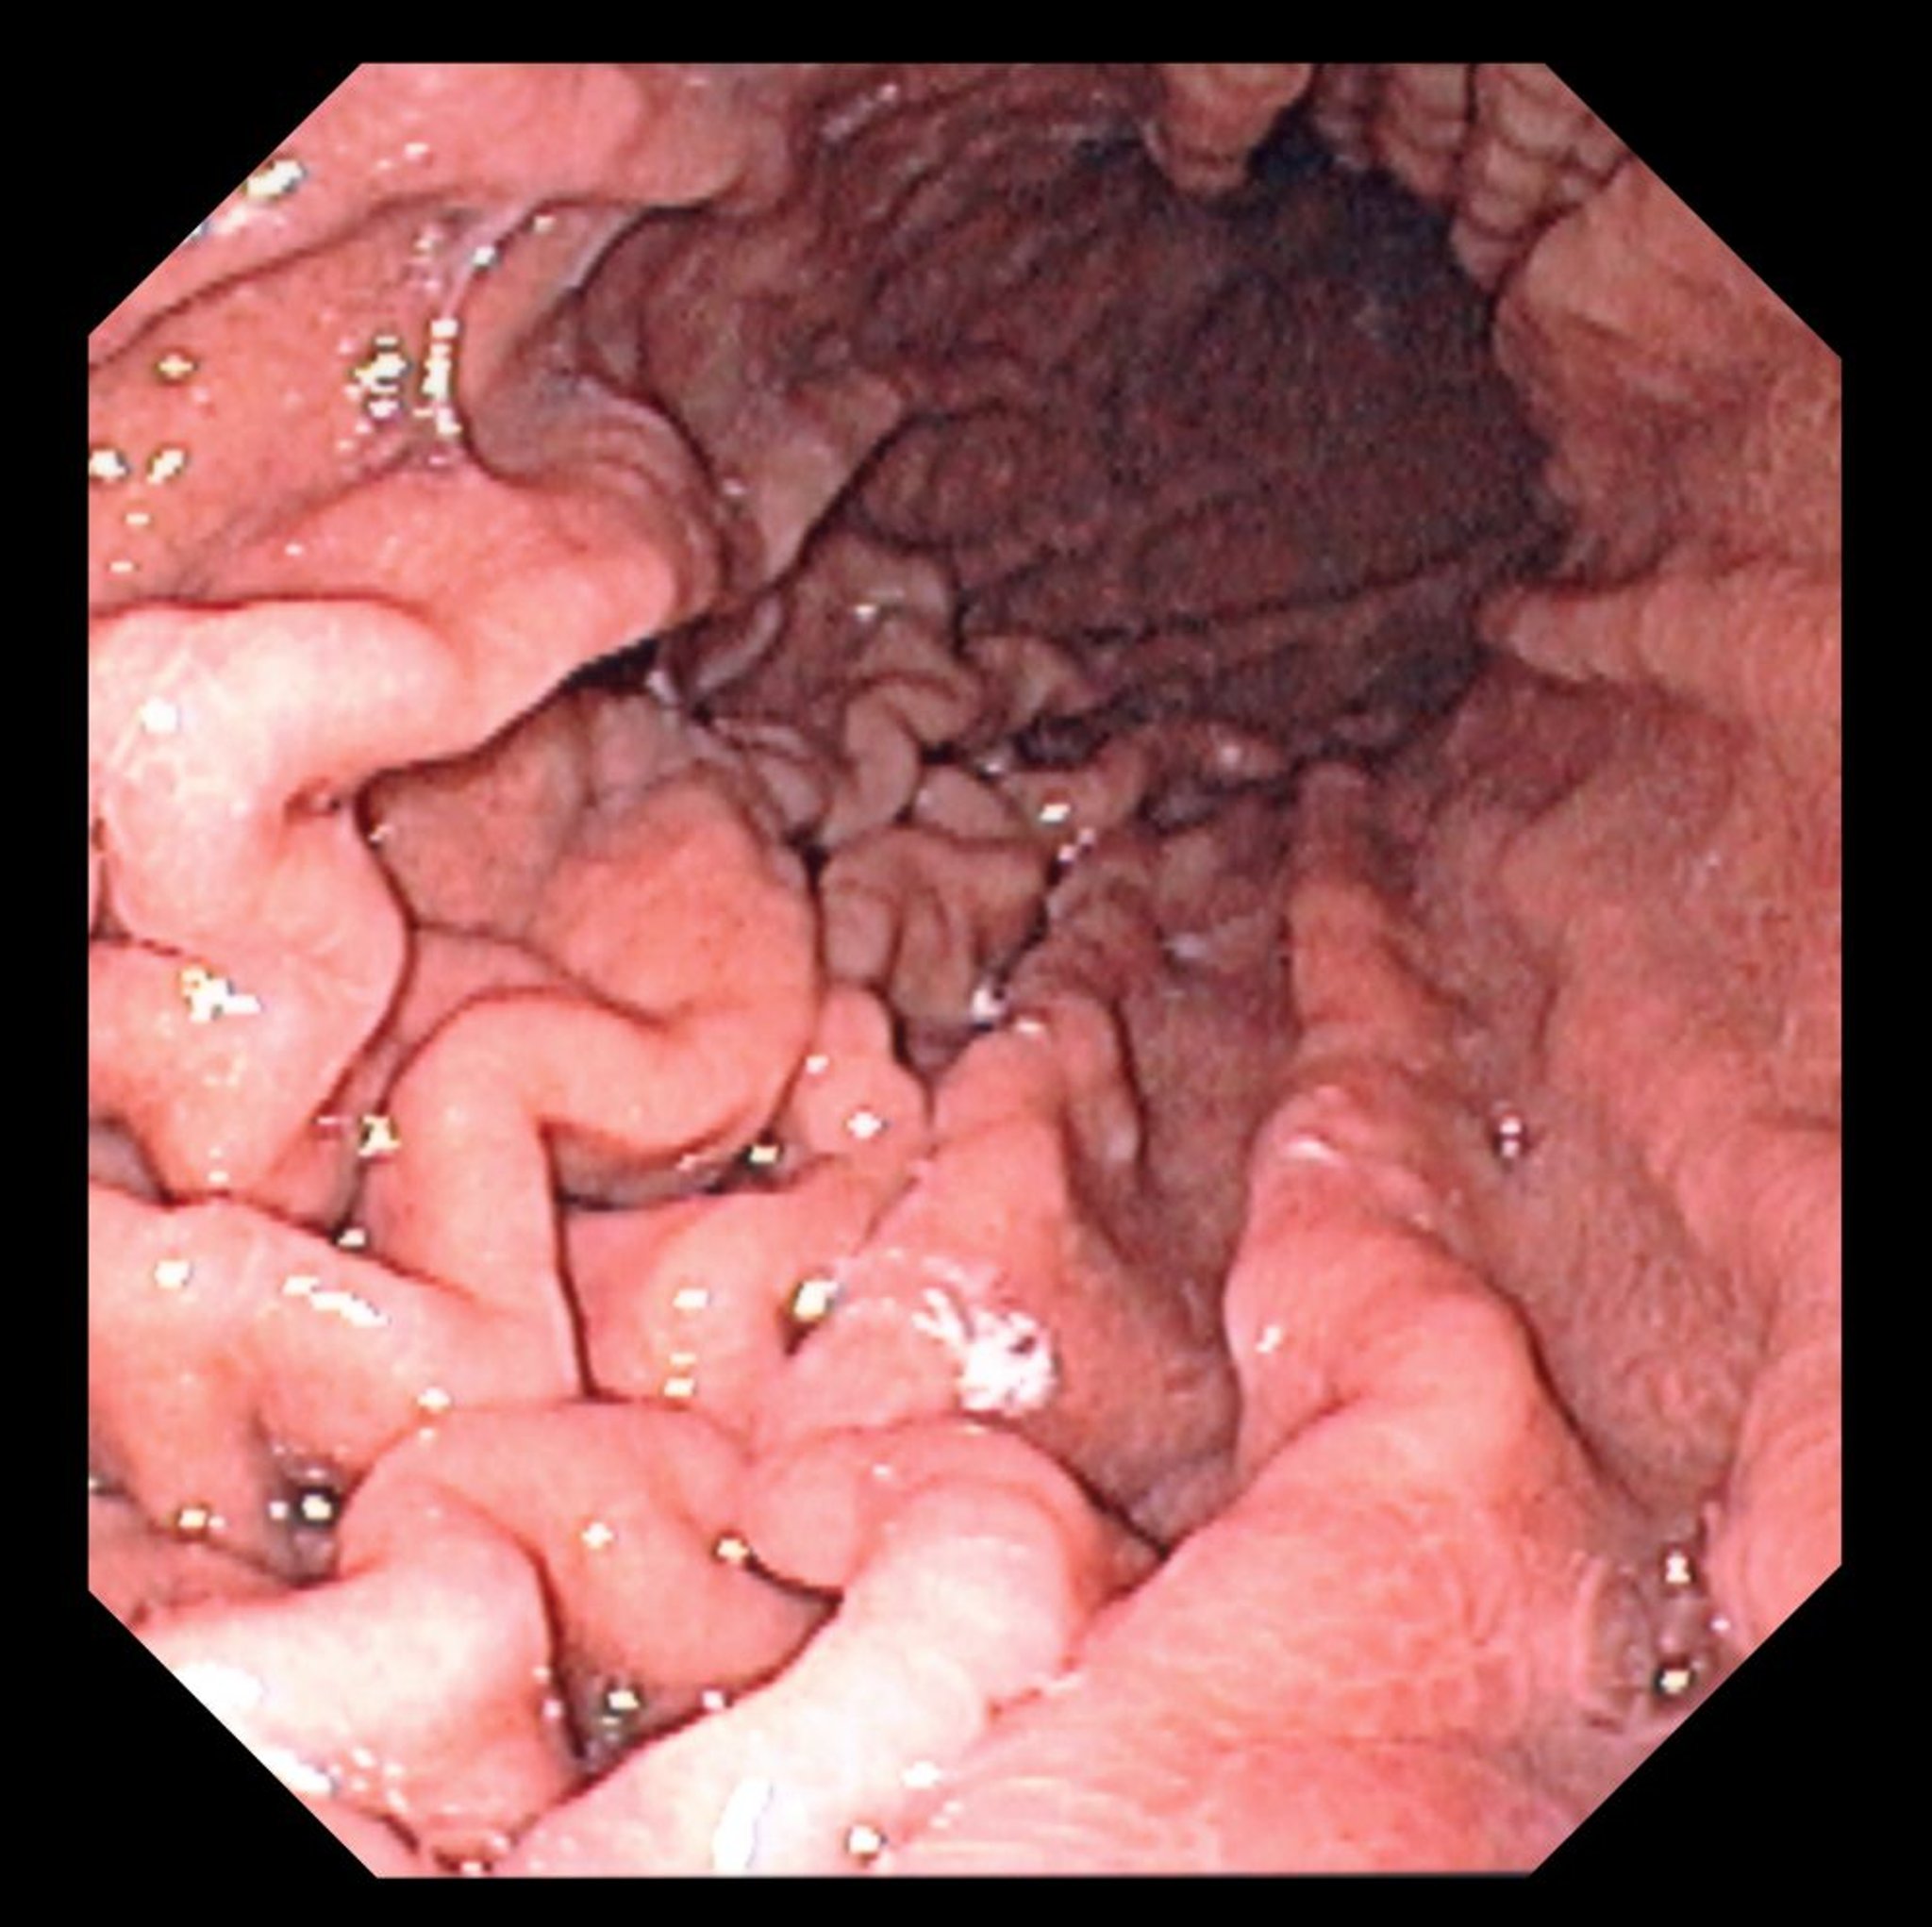

Esta fotografia muestra una vista endoscópica de un fondo de estómago normal con pliegues gástricos característicos.